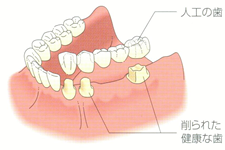

隣接する歯を1、2本失った場合

ブリッジの場合

・噛む際に、削られた歯に負担がかかり傷みやすい。

・歯根のない歯茎は、噛むことによる刺激がない為、次第にやせてしまう。

インプラントの場合

・健康な歯を利用しないため、自分の歯を保てる

・歯茎に噛む力がかかるので、歯茎を健康に保てる。